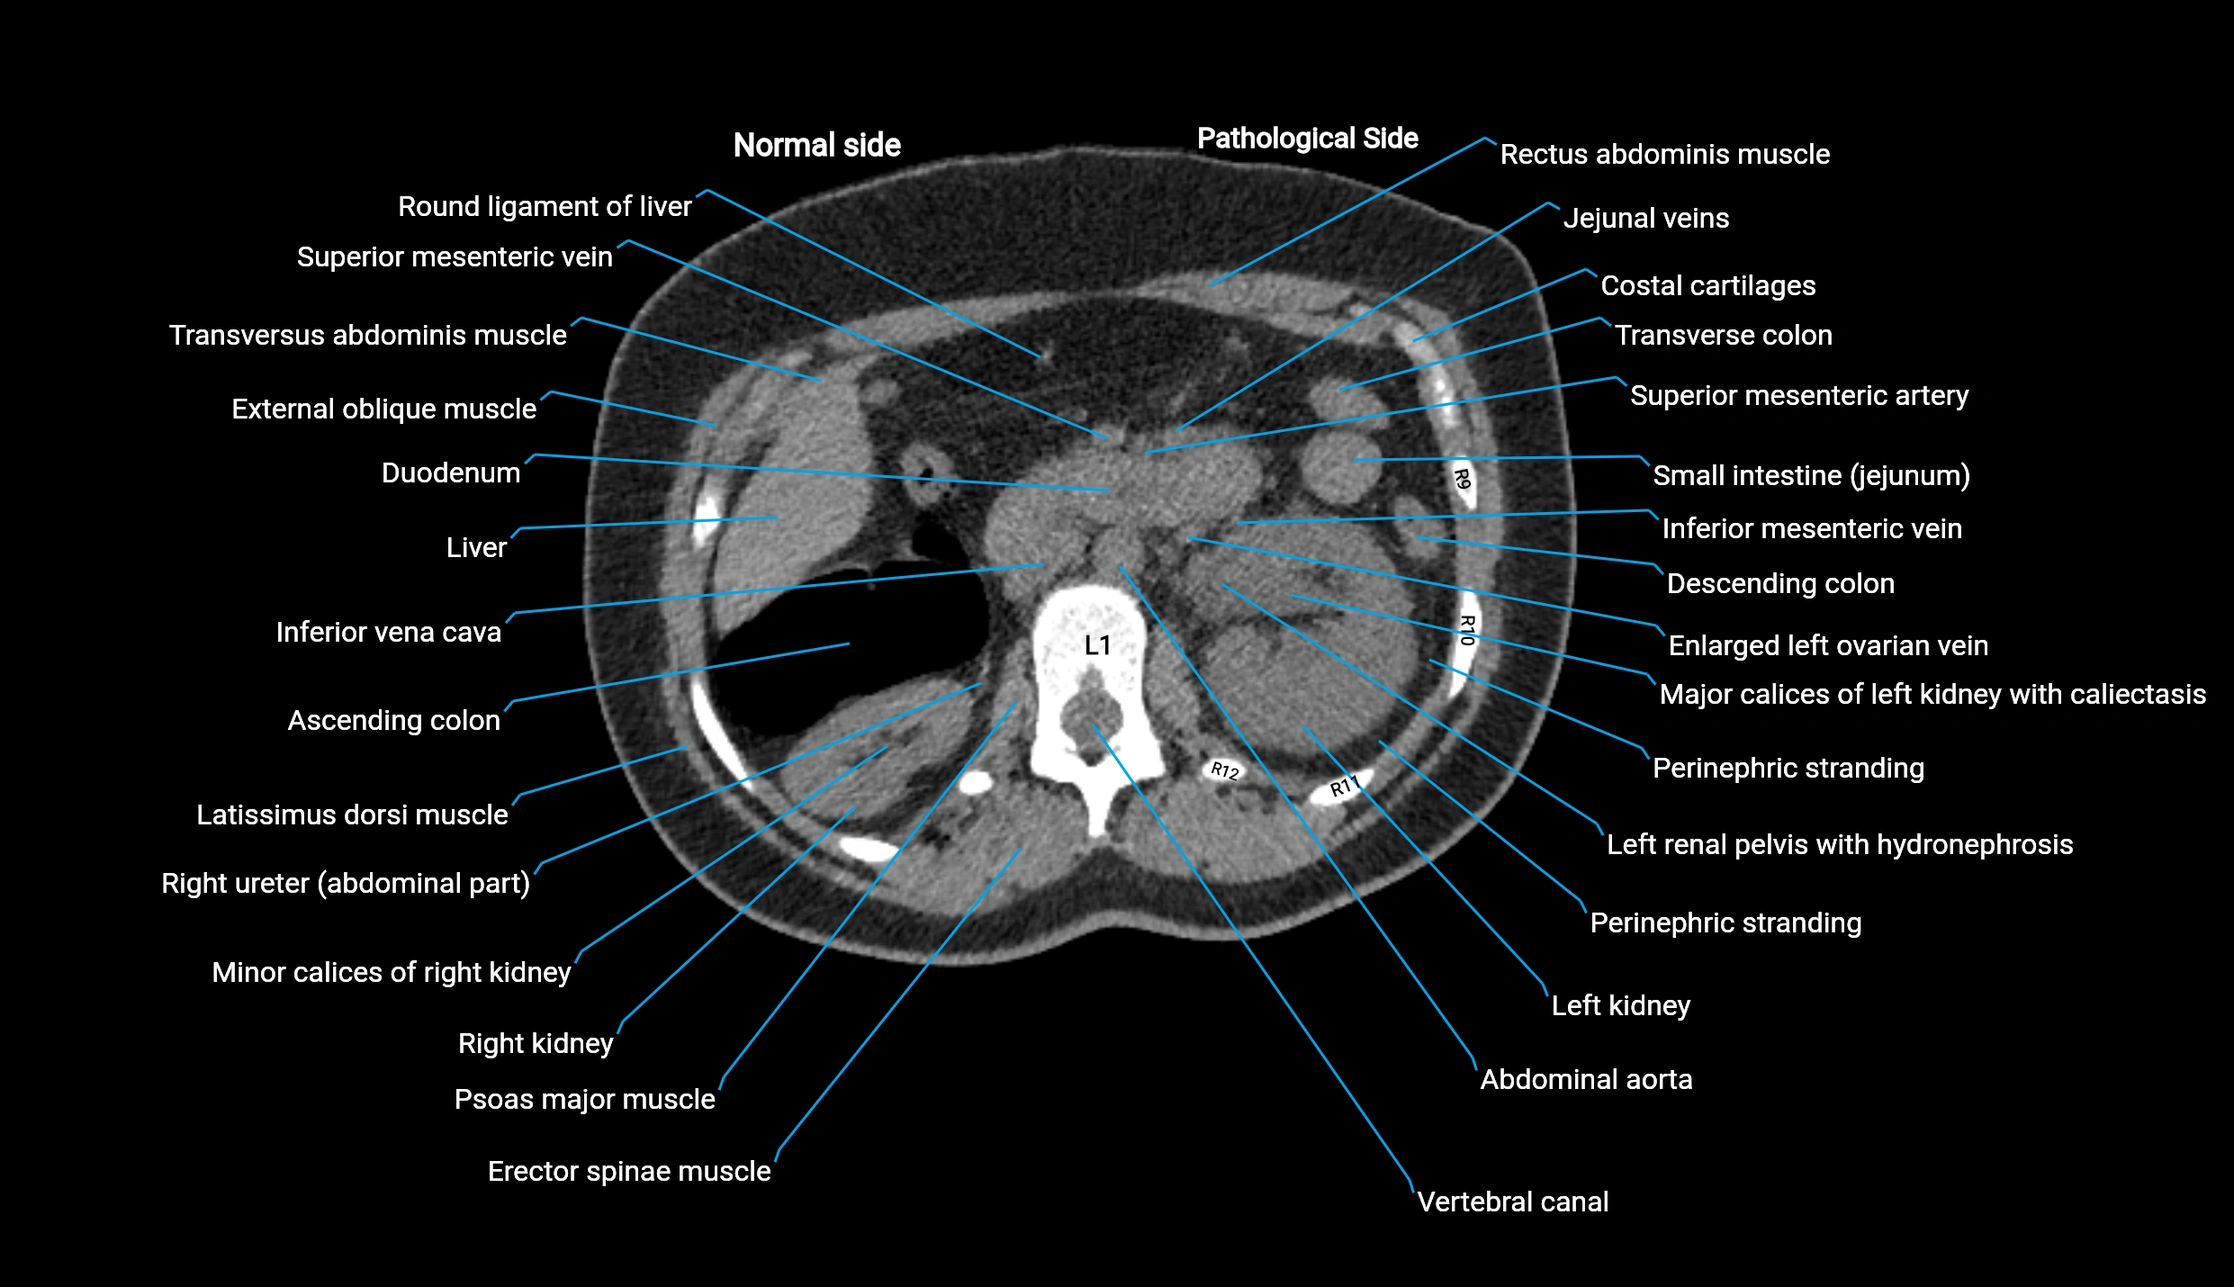

CT image

image